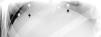

Hombre de 29 años con dolor abdominal de 48 h de evolución. El interrogatorio clínico, la exploración física y los hallazgos radiológicos fueron compatibles con apendicitis aguda complicada (fig. 1). Durante la laparoscopia se diagnosticó síndrome de Valentino (figs. 2 y 3). Se realizó apendicectomía, cierre primario con parche de Graham, toma de biopsia, lavado de cavidad y colocación de drenajes vía laparoscópica, con adecuada evolución posquirúrgica. En el nuevo análisis de la placa simple de abdomen se observó aire libre subdiafragmático (fig. 4).